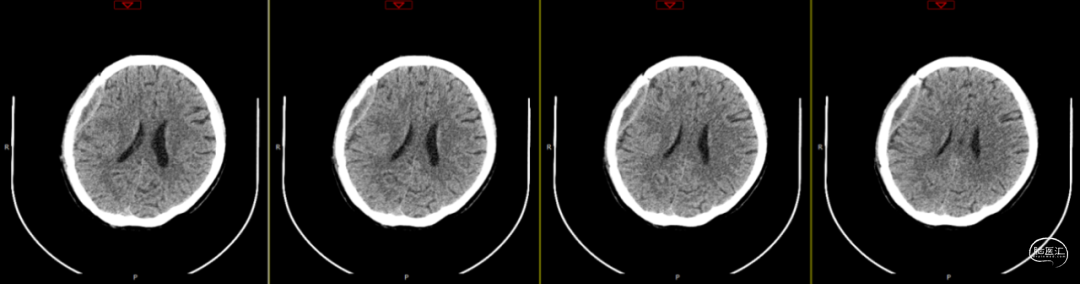

2024-07-21 08:58:55术后58天复查(如上图)。

术后58天颅脑磁共振平扫(如上图):右侧额顶颞部见斑片状异常信号,呈片状T1WI低、T2WI稍高信号影,T2FLAIR呈稍高信号,边界清,右侧额顶颞叶脑组织受压,DWI(b=1000)呈混杂高信号,相应ADC呈混杂高信号影。